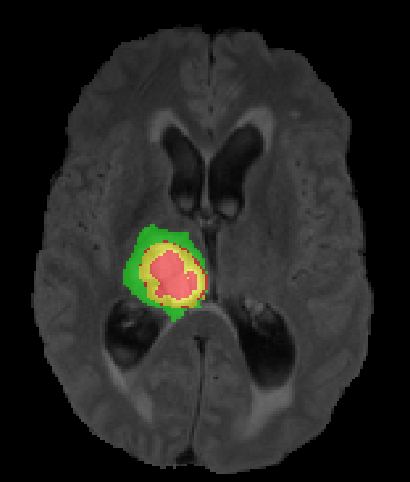

(a) Input images (b) Semantic Labels (c) Seg-Net+EG-CNN (d) Seg-Net

Geirhos et al. [35] empirically demonstrated that common CNN architectures are biased towards recognizing textures in the image, not object shape representations. This is in contrast to how humans normally segment images. In medical imaging for instance, expert manual segmentation often relies on the boundaries of anatomical structures; for example, to manually segment a liver, a medical practitioner usually identifies intensity edges first and subsequently fills the interior region in the segmentation mask. CNNs, which predominantly learn texture abstractions, often yield imprecise boundary delineations. Thus, CNN predictions often need to be post-processed to compensate for the shape details that the model fails to learn during training.

We argue that the sub-optimal paradigm of processing different abstractions within a single CNN pipeline can be remedied through the effective processing of information in a structured manner. Consequently, we devise strategies for disentangling the edge and texture information within a single training pipeline. Figure 2 illustrates how our proposed module, dubbed EG-CNN, can be paired with any existing CNN encoder-decoder to improve segmentation quality near intensity edges. We have applied our EG-CNN to the tasks of brain and liver tumor segmentation in medical images (Figure 3).

(1) Brain MR (2) Liver MR (3) Liver CT (4) Lung CT